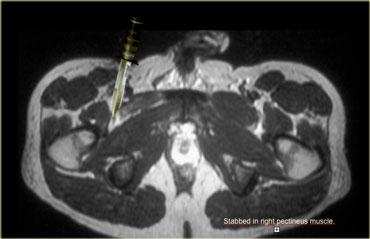

Bên trái là hình ảnh của một bệnh nhân bị thương do dao.

Người đàn ông này bị vợ bắt gặp khi đang ngoại tình với người phụ nữ khác và bị đâm vào vùng bẹn.

Hậu quả là cơ lược bên phải của ông bị rách.

Chụp cộng hưởng từ thường không được chỉ định trong trường hợp vết rách, vì những bệnh nhân này thường được đưa thẳng đến phòng cấp cứu hoặc phòng mổ để phẫu thuật thăm dò, nhưng trường hợp này minh họa rõ nét hình ảnh cơ bị teo và mô sẹo.